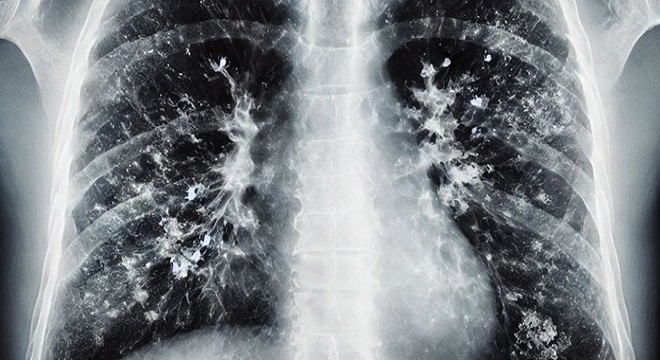

Zatürrenin grip ya da soğuk algınlığıyla karıştırılabileceğini belirten Prof. Dr. Özlü, "Bu tür enfeksiyonlar genelde üst solunum yollarında yerleşir. Oradan başlar ve nezle, soğuk algınlığı, farenjit, sinüzit gibi üst solunum yolu enfeksiyonlarına yol açar. Bazen de alt solunum yollarına ilerleyerek bronşit, bronşiolit gibi hafif hastalıklara yol açabilir. Fakat zatürre, bu hastalıklar arasında en ağır olanıdır. Maalesef, şu sıralar pek çok hasta zatürreyi fark edemiyor ve teşhiste geç kalıyor. Oysa zatürrede erken tanı çok önemli. Hekimin, 4 saat içinde doğru tedaviye başlaması, zatürreye bağlı ölümleri anlamlı şekilde azaltıyor" ifadelerini kullandı.

Zatürre tanısında en önemli belirtilerin nefes darlığı ve öksürük olduğunu ifade eden Özlü, "Şikayetleriniz tedaviyle ya da tedavisiz olarak ilk birkaç gün içinde azaldıktan sonra tekrar ikinci bir atak yaşanıyorsa; ateşlenme ve şikayetlerde artış oluyorsa bu da zatürrenin eklendiğini gösterebilir. Nefes darlığı çok önemli bir belirti. Özellikle nefes alıp vermekte zorlanıyorsanız, özellikle bebeklerde ve yaşlılarda solunum sayısının dakikada 24'ün üzerine çıkması, nefes alıp verirken hırıltı olması, bebeklerde burun kanatlarının solunuma eşlik etmesi, nabız sayısının dakikada 120'nin üzerine çıkması gibi durumlar zatürre olasılığını güçlendirir. Öksürük de önemli bir belirti. Zatürrede öksürük genellikle yaş öksürüktür. Yani balgamlıdır. Balgamın koyu renkli olması; kahverengi, koyu sarı, koyu yeşil gibi ve kıvamlı olması zatürre ihtimalini artırır. Ateşin çok yüksek olmasıyla birlikte yan ağrısı dediğimiz, öksürürken ya da nefes alırken batıcı şekilde hissedilen bir yan ağrısı varsa, bu da zatürreye işaret edebilir" dedi.